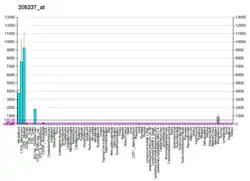

Proteins of the ficolin family consist of a leader peptide, a short N-terminal segment, followed by a collagen-like domain, and a C-terminal fibrinogen-like domain. The name of ficolin was derived from the latter two domains. The collagen-like and the fibrinogen-like domains are also found in other proteins such as tenascins, while the former is also found in complement protein C1q and collectins, which include mannose-binding lectin and lung surfactant proteins. Ficolins selectively recognize acetylated compounds. M-ficolin encoded by FCN1 is predominantly expressed in the peripheral blood leukocytes, and has been postulated to function as a plasma protein with elastin-binding activity. Several SNPs have been described in the FCN1 gene with impact on serum concentrations of M-ficolin and the ligand binding ability. M-ficolin levels reflect disease activity and predict remission in early rheumatoid arthritis.

Arthritis Rheum. 2013 Dec;65(12):3045-50. doi: 10.1002/art.38179. M-ficolin levels reflect disease activity and predict remission in early rheumatoid arthritis. Ammitzbøll CG1, Thiel S, Jensenius JC, Ellingsen T, Hørslev-Petersen K, Hetland ML, Junker P, Krogh NS, Østergaard M, Stengaard-Pedersen K.